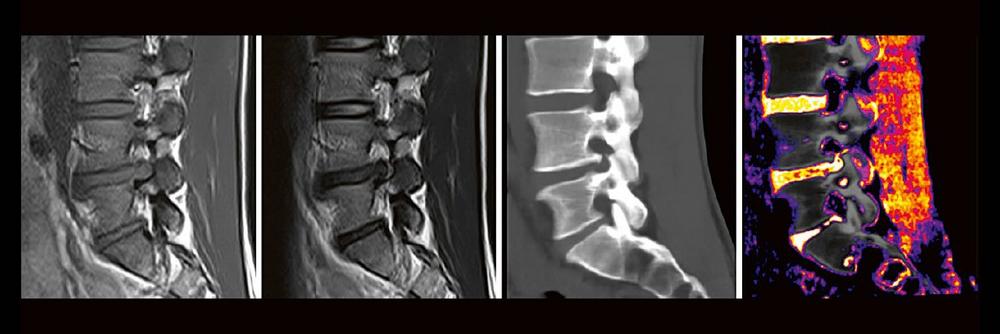

Professor Dr. med. Matthias PumbergerPD Dr. med. Torsten Diekhoff Die Dual-Energy-Computertomographie (DECT) hat für viele klinische Anwendungen bereits Einzug in die Praxis genommen. Für die Behandlung von Wirbelsäulenerkrankungen sind besonders die Darstellung von Knochenmarkveränderungen (z. B. bei osteoporotischen Frakturen) und der Bandscheibe (z. B. bei Bandscheibenvorfällen) interessant und werden intensiv beforscht. Hierdurch versprechen wir uns